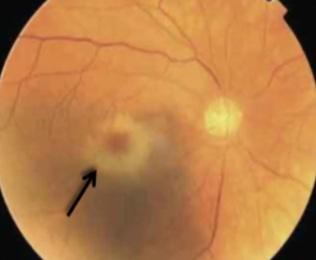

Fondo de ojo

♦ Lesiones atróficas amarillentas (toxoplasma)

♦ Lesiones necróticas hemorrágicas (citomegalovirus)

Figura 41. Coreorretinitis por toxoplasma: Lesiones atróficas amarillentas Figura 42. Coreorretinitis por citomegalovirus: Lesiones necróticas hemorrágicas Figura 40. Toxoplasmosis es la causa más frecuente de coreorretinitis